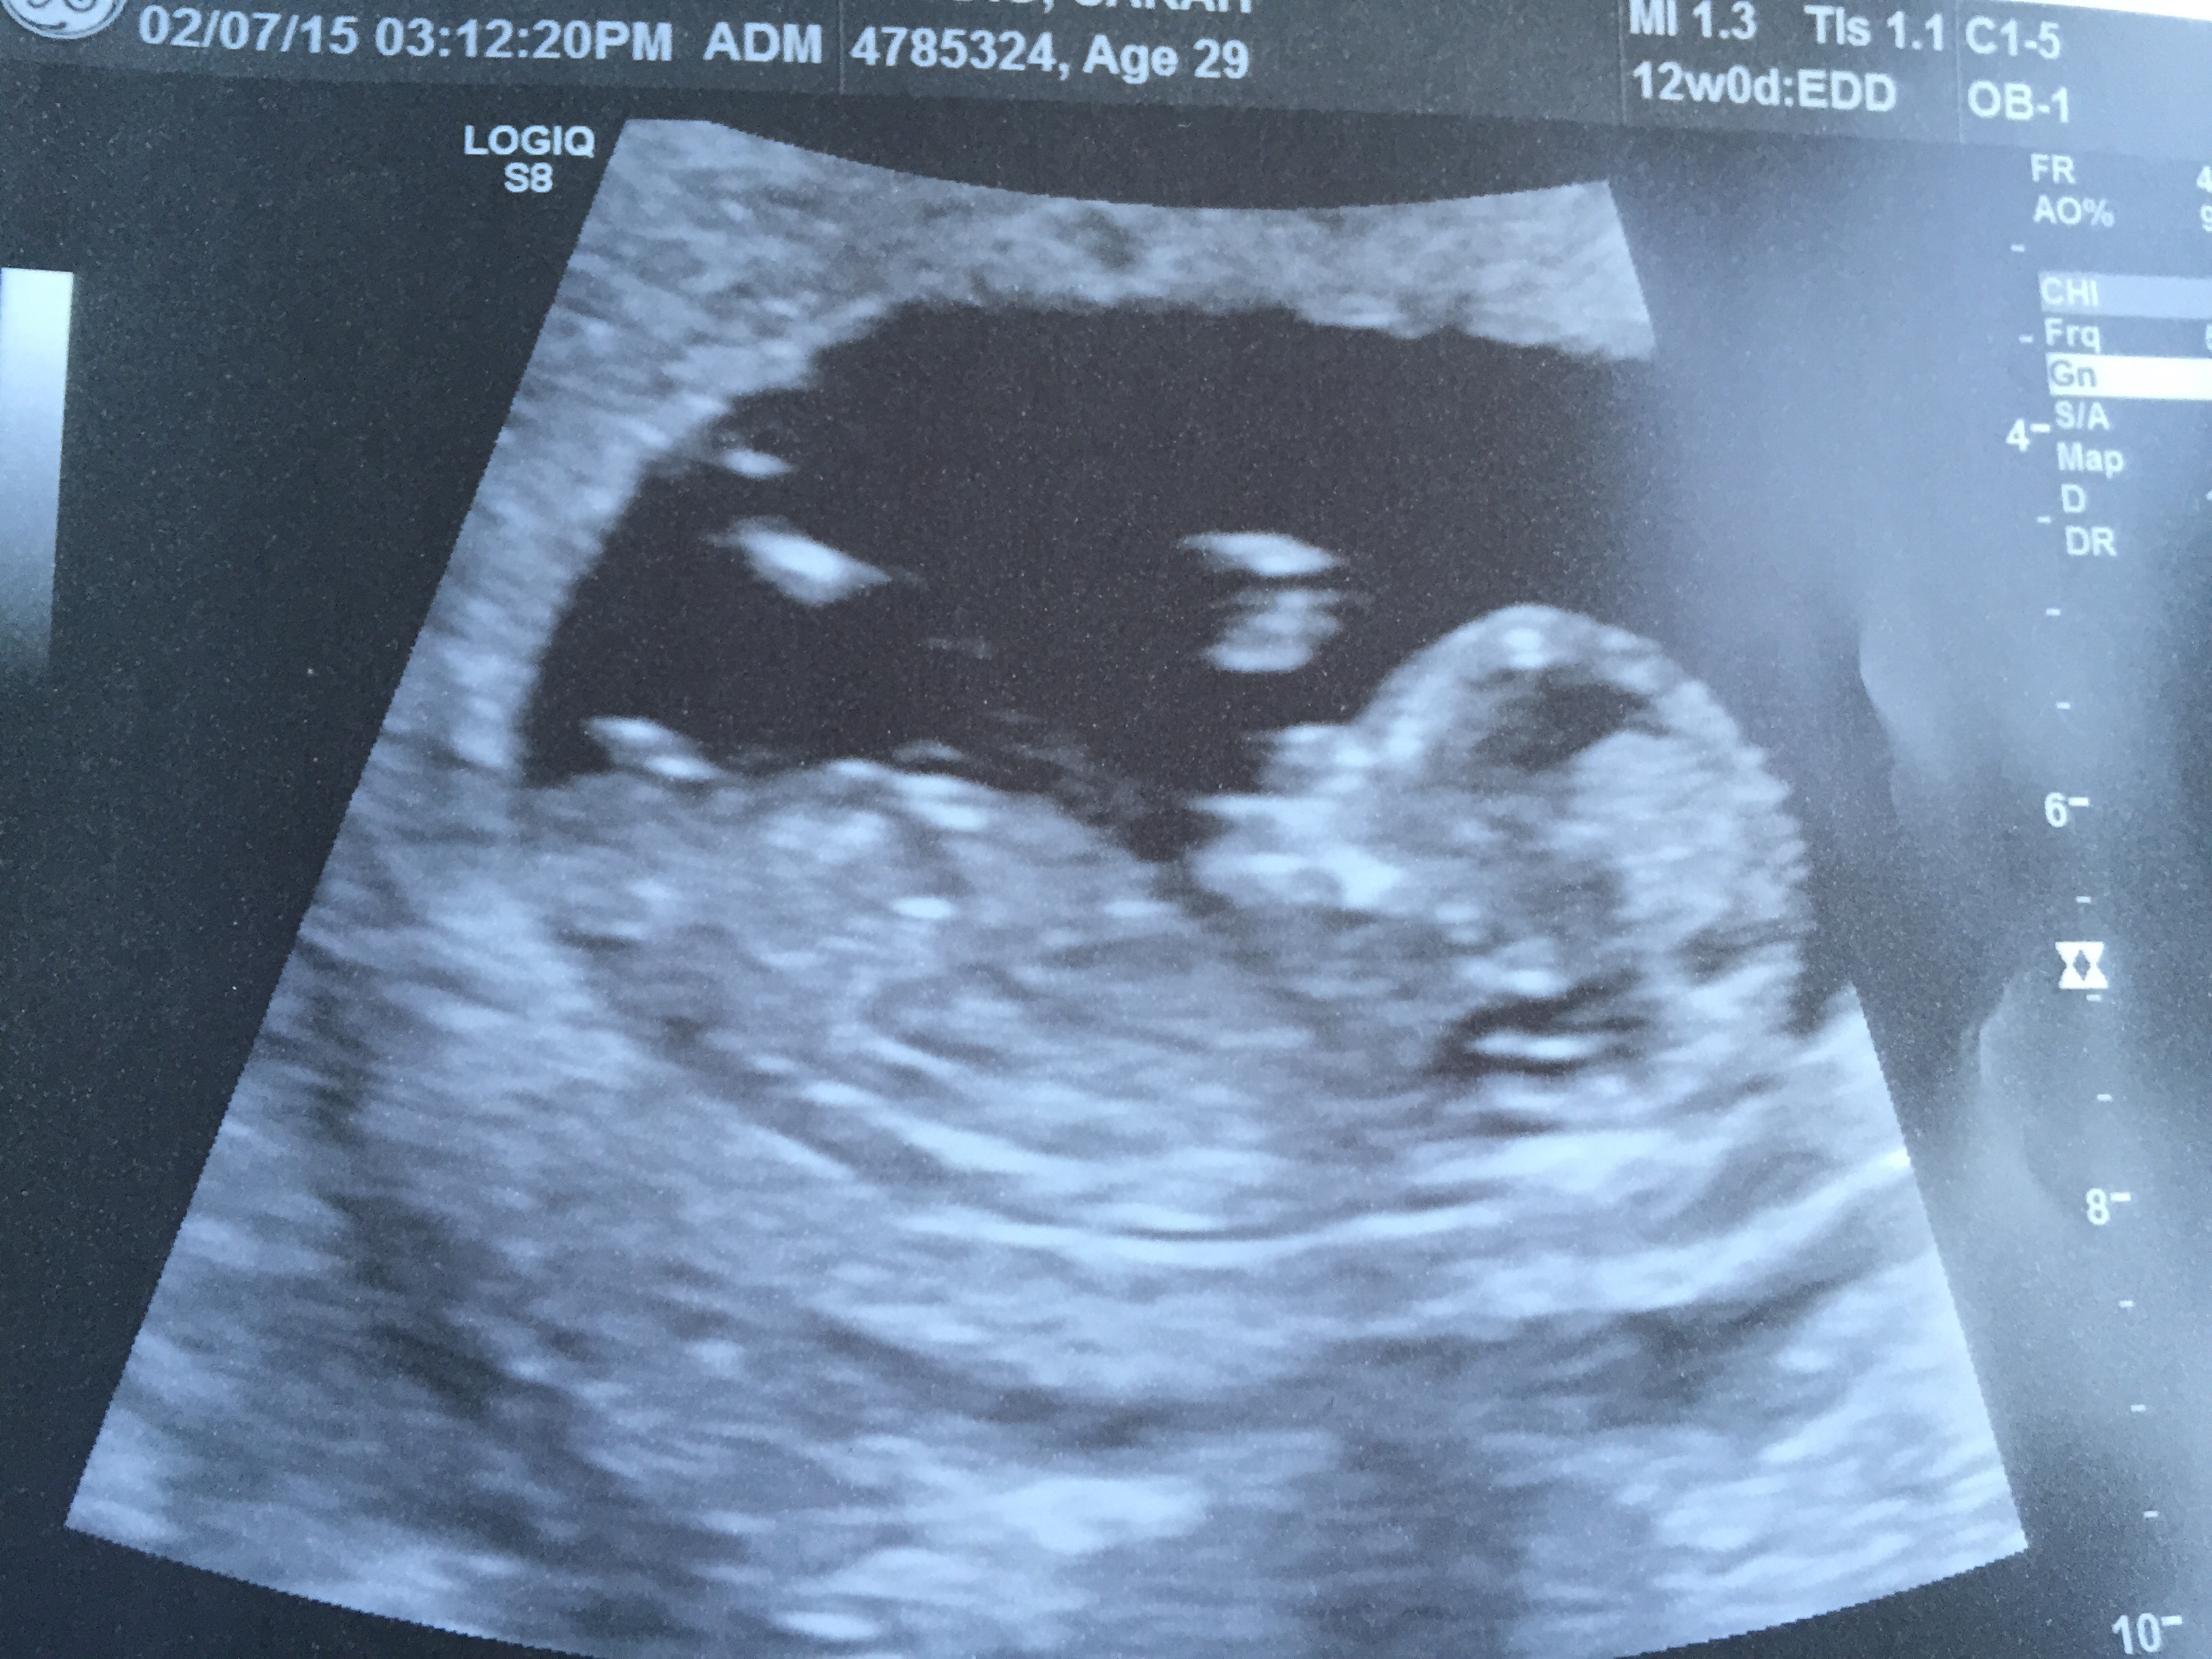

• Please do mine! Anatomy scan isn't until September 1... This is at 13 weeks and 2 days...